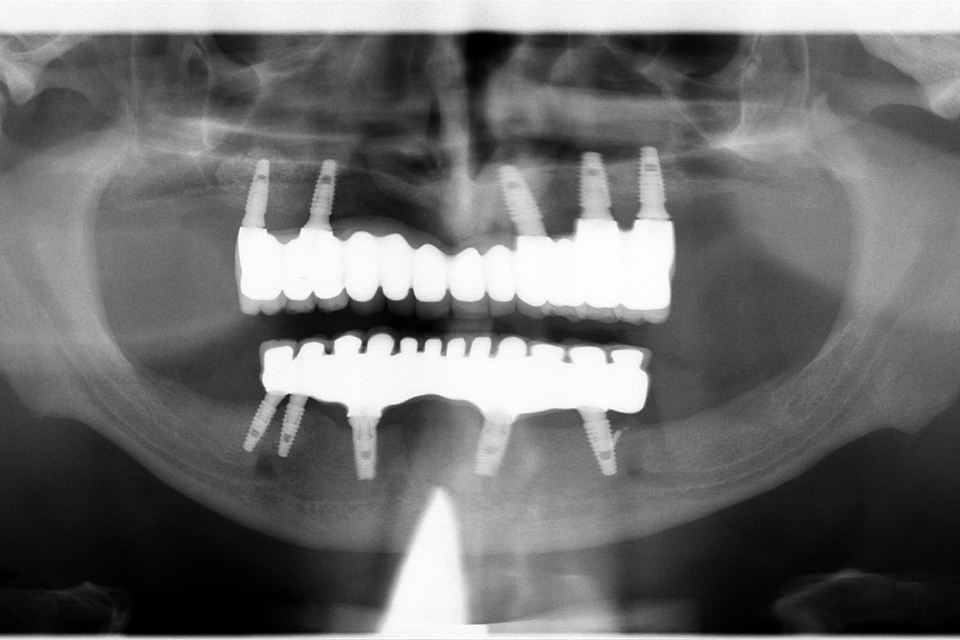

Pacientul a revenit in cabinet pentru consultatia anuala de intretinere, implanturile fiind inserate in urma cu 5 ani.

Cazul a fost unul foarte dificil pacientul fiind purtator vechi de proteze totale acrilice bimaxilar. A fost nevoie de 2 sinus lifting-uri si 5 implanturi pentru arcada superioara, iar pentru arcada inferioara s-au realizat aditii osoase (bilateral), prin tehnica Khoury.

Rezultatele au fost spectaculoase, fara sa fi intervenit resorbtii de natura osasa sau gingivala, pacientul fiind foarte multumit.